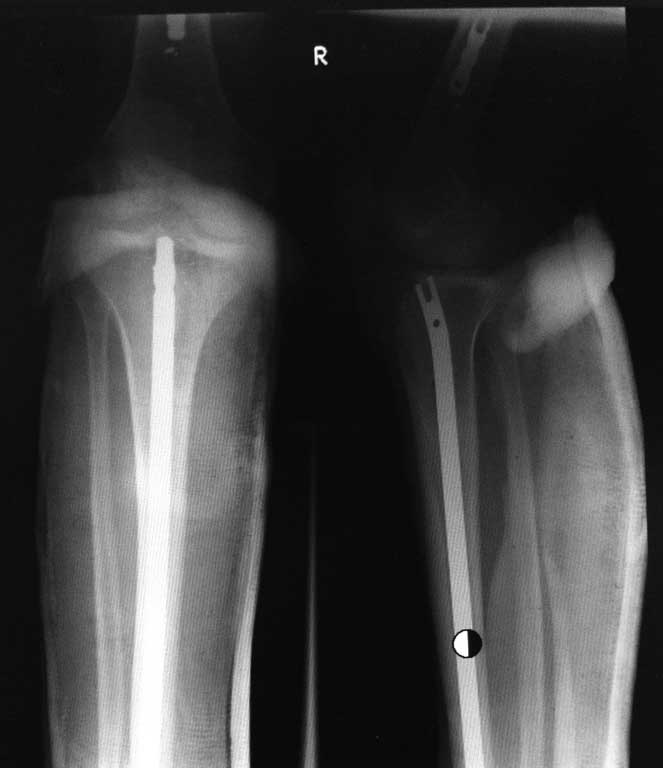

Коллеги, помогите определиться с тактикой лечения сложного пациента Пациент 19 лет, лечится с 17 лет, когда был перелом костей н/3 голени и был оперирован пластиной. Через год - повторный перелом с повреждением пластины (по видимому ложный сустав) , соответственно вторая операция - БИОС б/бецовой кости стержнем ChM с биодеградирующей крошкой в область ложного сустава на метафизе и фиксацией серкляжами + остеосинтез м/берцовой кости пластиной.Далее через несколько месяцев после операции осенью 2012 года также после нагрузок ломается уже стержень в области метафиза с деформацией голени. В связи с чем оперируется уже в третий раз в январе 2012 г., где после длительной операции удалить стержень до конца не удается (на снимках все дистальные винты стержня и сломанный его фрагмент, а также серкляжи - удалены), ставится пластина(!)- видимо фиксировали тем, что было под рукой. Как выяснилось позже, был план по установке АВФ, но проксимальный фрагмент стержня оказался из разряда неудалимых и, пришлось оставлять его (!).На сегодня ситуация следующая. Парень обратился на консультацию, нога в лонгете. На снимках - деформация н/3 голени с миграцией пластины, часть стержня в проксимальном фрагменте, перелом пластины на малоберцовой кости. Кожа чистая, воспаления и свищей нет. Хотелось бы услышать Ваше мнение по тактике лечения.

Вчера не вышло выслать все фото. Последние снимки более более драматичные, как раз с куском проксимального стержня и пластиной что не к месту!

пластина для проксимального отдела плеча, заканчивающаяся на уровне ложного сустава, конечно не к месту.и вновь состояние мягкотканного компонента?.... Аппарат Илизарова. Суважением Ушаков С.